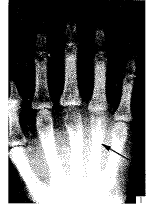

牛骨骨针在手部骨折中的应用

【摘要】 目的 介绍牛皮质骨骨针在手部骨折治疗中的应用 ......